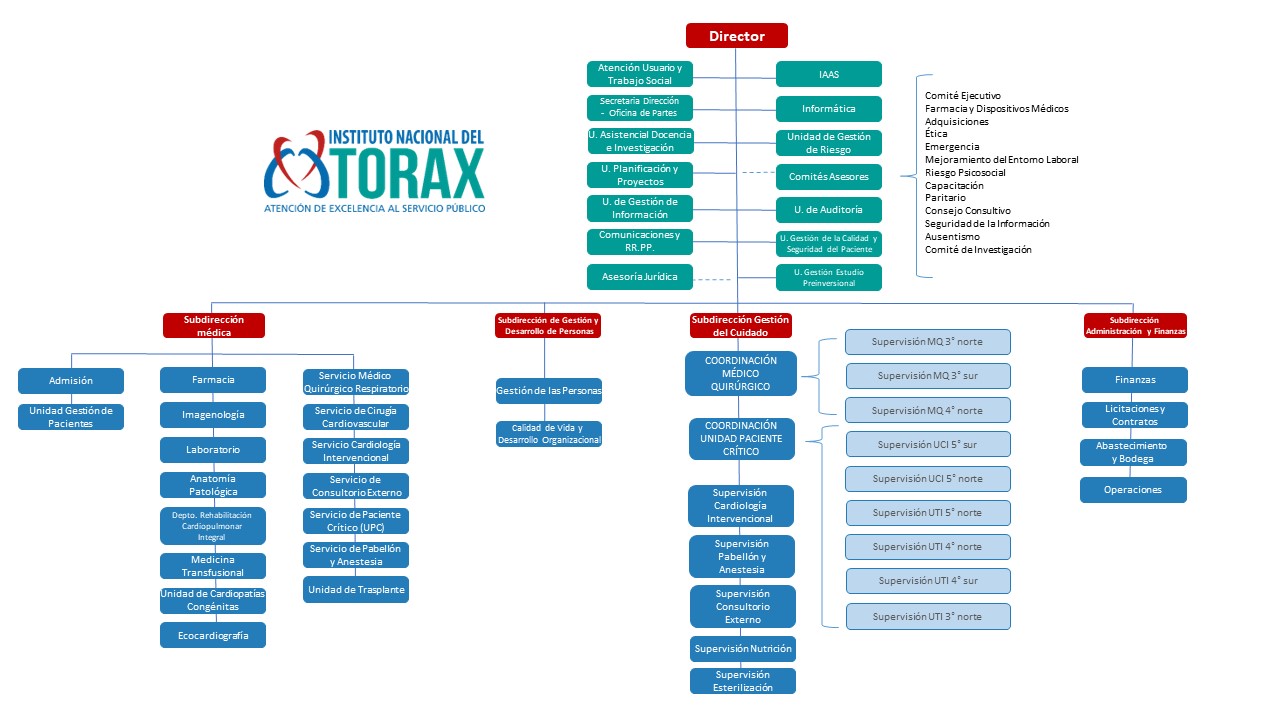

¿Cuál es el rol del INT dentro del Programa Nacional Contra la Tuberculosis?

Los médicos que fundaron el Instituto Nacional del Tórax fueron médicos tisiólogos, formados en Europa; ellos crearon el Hospital de Tórax para el tratamiento integral de la tuberculosis y otras enfermedades respiratorias. Además, el instituto sigue teniendo un importante rol en esta materia, contribuyendo con su experiencia a las normativas nacionales de la tuberculosis y realizando semanalmente la reunión de tuberculosis donde se presentan los casos más complejos.

Asimismo, el Laboratorio de la Tuberculosis del INT cumple una labor muy importante en la detección de casos en toda la zona. En la unidad se procesan todas las muestras provenientes de los 21 CESFAM del Servicio de Salud Metropolitano Oriente, siete hospitales y tres instituciones privadas.